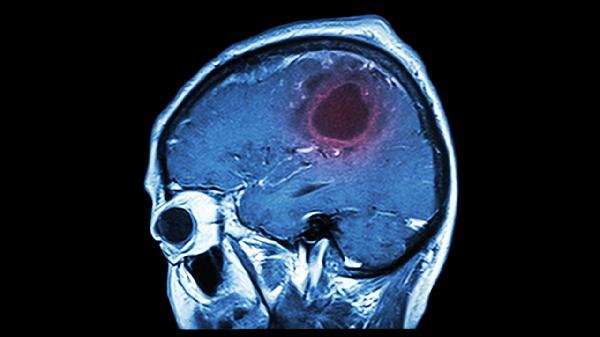

脑血栓可通过生活干预、药物治疗、手术治疗等方式治疗。脑血栓通常由动脉粥样硬化、高血压、糖尿病、心房颤动、高脂血症等原因引起。

颈动脉内膜切除术适用于颈动脉狭窄超过70%的无症状患者。机械取栓术通过导管介入清除大血管血栓,最佳实施时间为发病6小时内。部分大面积脑梗死患者可能需去骨瓣减压术降低颅内压。